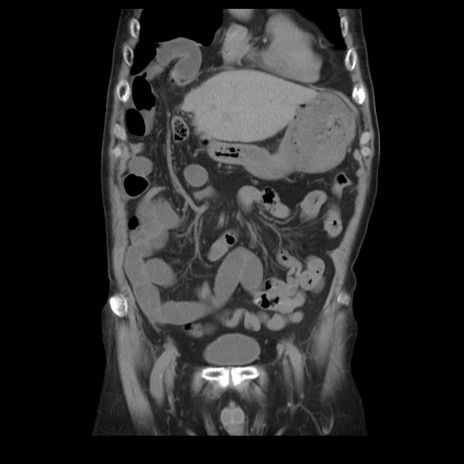

症例21(冠状断像)

【症例】70歳代男性

【主訴】腹痛

【現病歴】肝硬変・肝細胞癌にてかかりつけの方。約9時間前に食後より腹痛出現。症状が徐々に増悪し、嘔吐出現したため来院。

【既往歴】肝硬変、肝細胞癌(RFA、TACE後)

【身体所見】意識清明、表情苦悶様、BT 36℃、BP 129/78mmHg、P 88bpm、SpO2 97%(RA)、右上腹部から心窩部にかけて圧痛あり、反跳痛なし、筋性防御あり。

【データ】WBC 5800、CRP 0.16